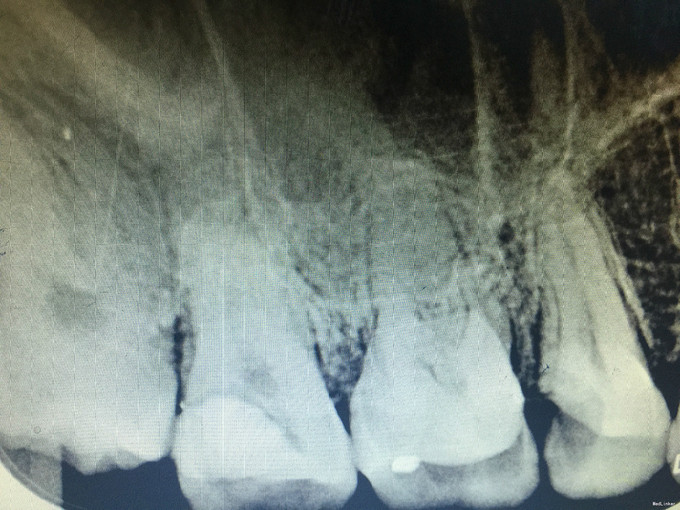

诊断:17继发龋 治疗:经患者知情同意后,17局麻去除原有充填物降牙合,开髓拔髓寻找根管口,建立直线通路,扩通根管,确定工作长度。S3/EDTA凝胶镍钛器械,低浓度次氯酸钠冲洗根管,预备至35/04,氢氧化钙诊间封药,一周后复诊,试主尖X线示恰充,试干根管,导AH-PLUS糊剂,VDW热压胶垂直加压根充,术后见根管恰充,暂封调合抛光。术后观察嵌体修复。

对于树脂充填一定要去净腐质避免继发龋的发生。